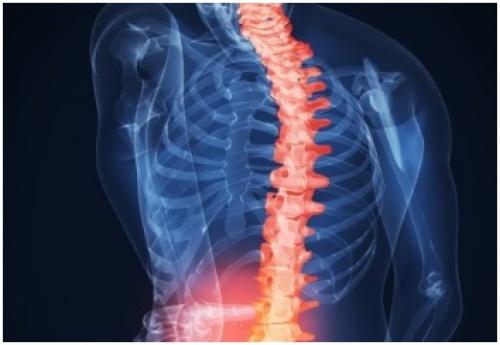

Средства для хрящевой ткани. Как восстановить хрящевую ткань позвоночника?

Восстановление хрящевой ткани позвоночника возможно за счет приема хондропротекторов, витаминов, гормональных средств. Плюс к медикаментам идет нормализация питания и полный отказ от табакокурения и алкоголя. Начинать лечение не рекомендуется без ведома специалиста.

Как восстановить хрящевую ткань позвоночника?

Как обновить хрящ? При умеренных изменениях в хрящевой ткани позвоночника, специалисты назначают лекарственные препараты, витамины, рекомендуют наладить питание.